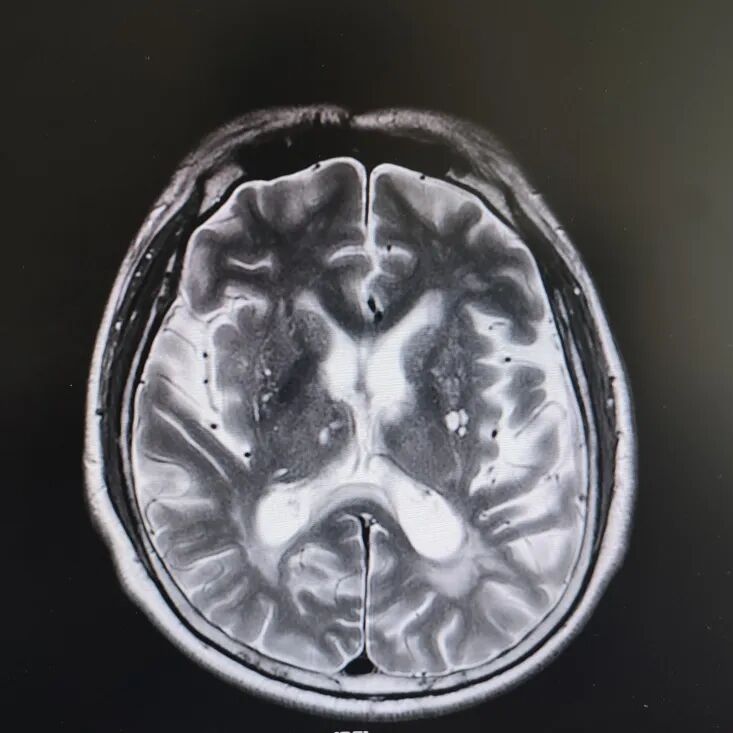

病房里还有另一位患者,来的时候情况更让人揪心:反应迟钝,表情呆滞,行动缓慢。头颅核磁显示脑萎缩明显,但查体发现肌张力、计算力、记忆力、定向力均正常,不符合典型血管性痴呆或阿尔茨海默病表现。

患者头部磁共振影像

凭着多年诊治疑难杂症的丰富经验,赵主任敏锐地意识到这“痴呆”可能是假象,背后另有隐情。他果断建议进一步做特殊感染筛查。果然,检查证实这位患者同样是感染了苍白密螺旋体!经过精准的抗感染治疗,奇迹发生了:患者的反应变快了,眼神灵活了,走路也恢复了正常步态。最终的诊断是“麻痹性痴呆”——一种由神经梅毒引起的、可治疗逆转的“痴呆”类型!